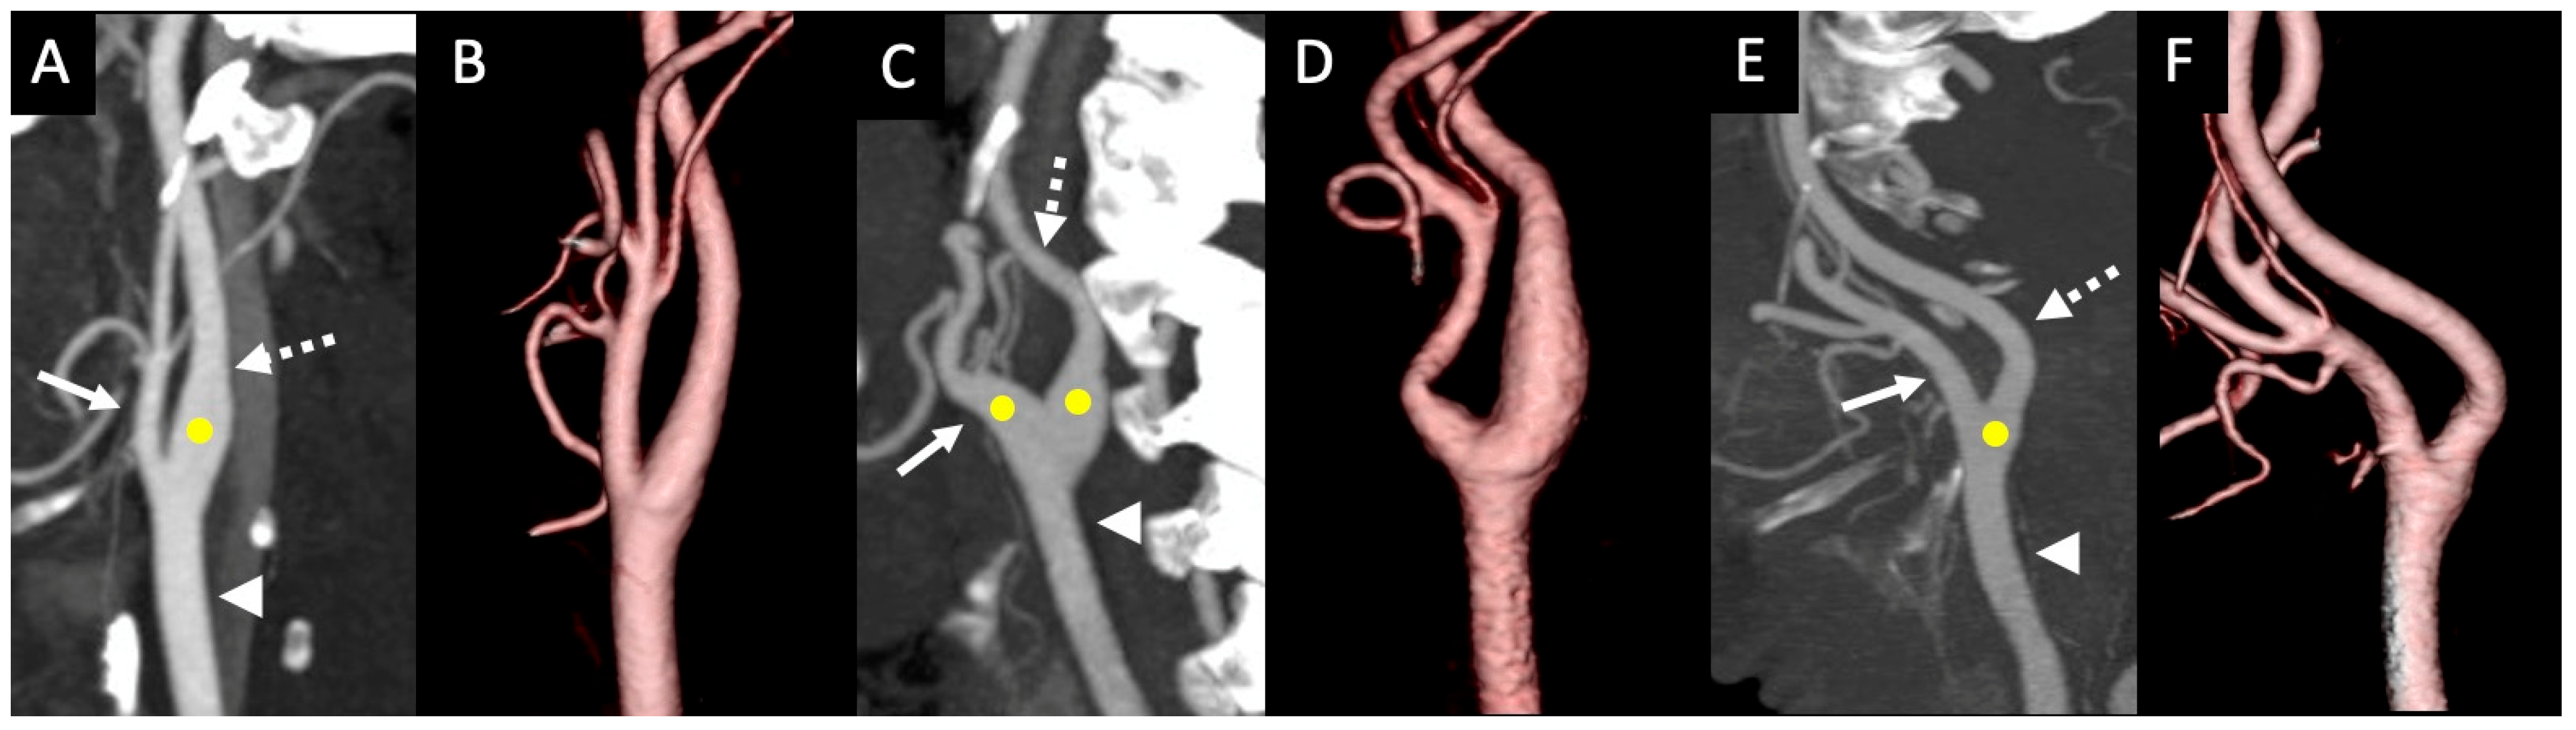

3. Results